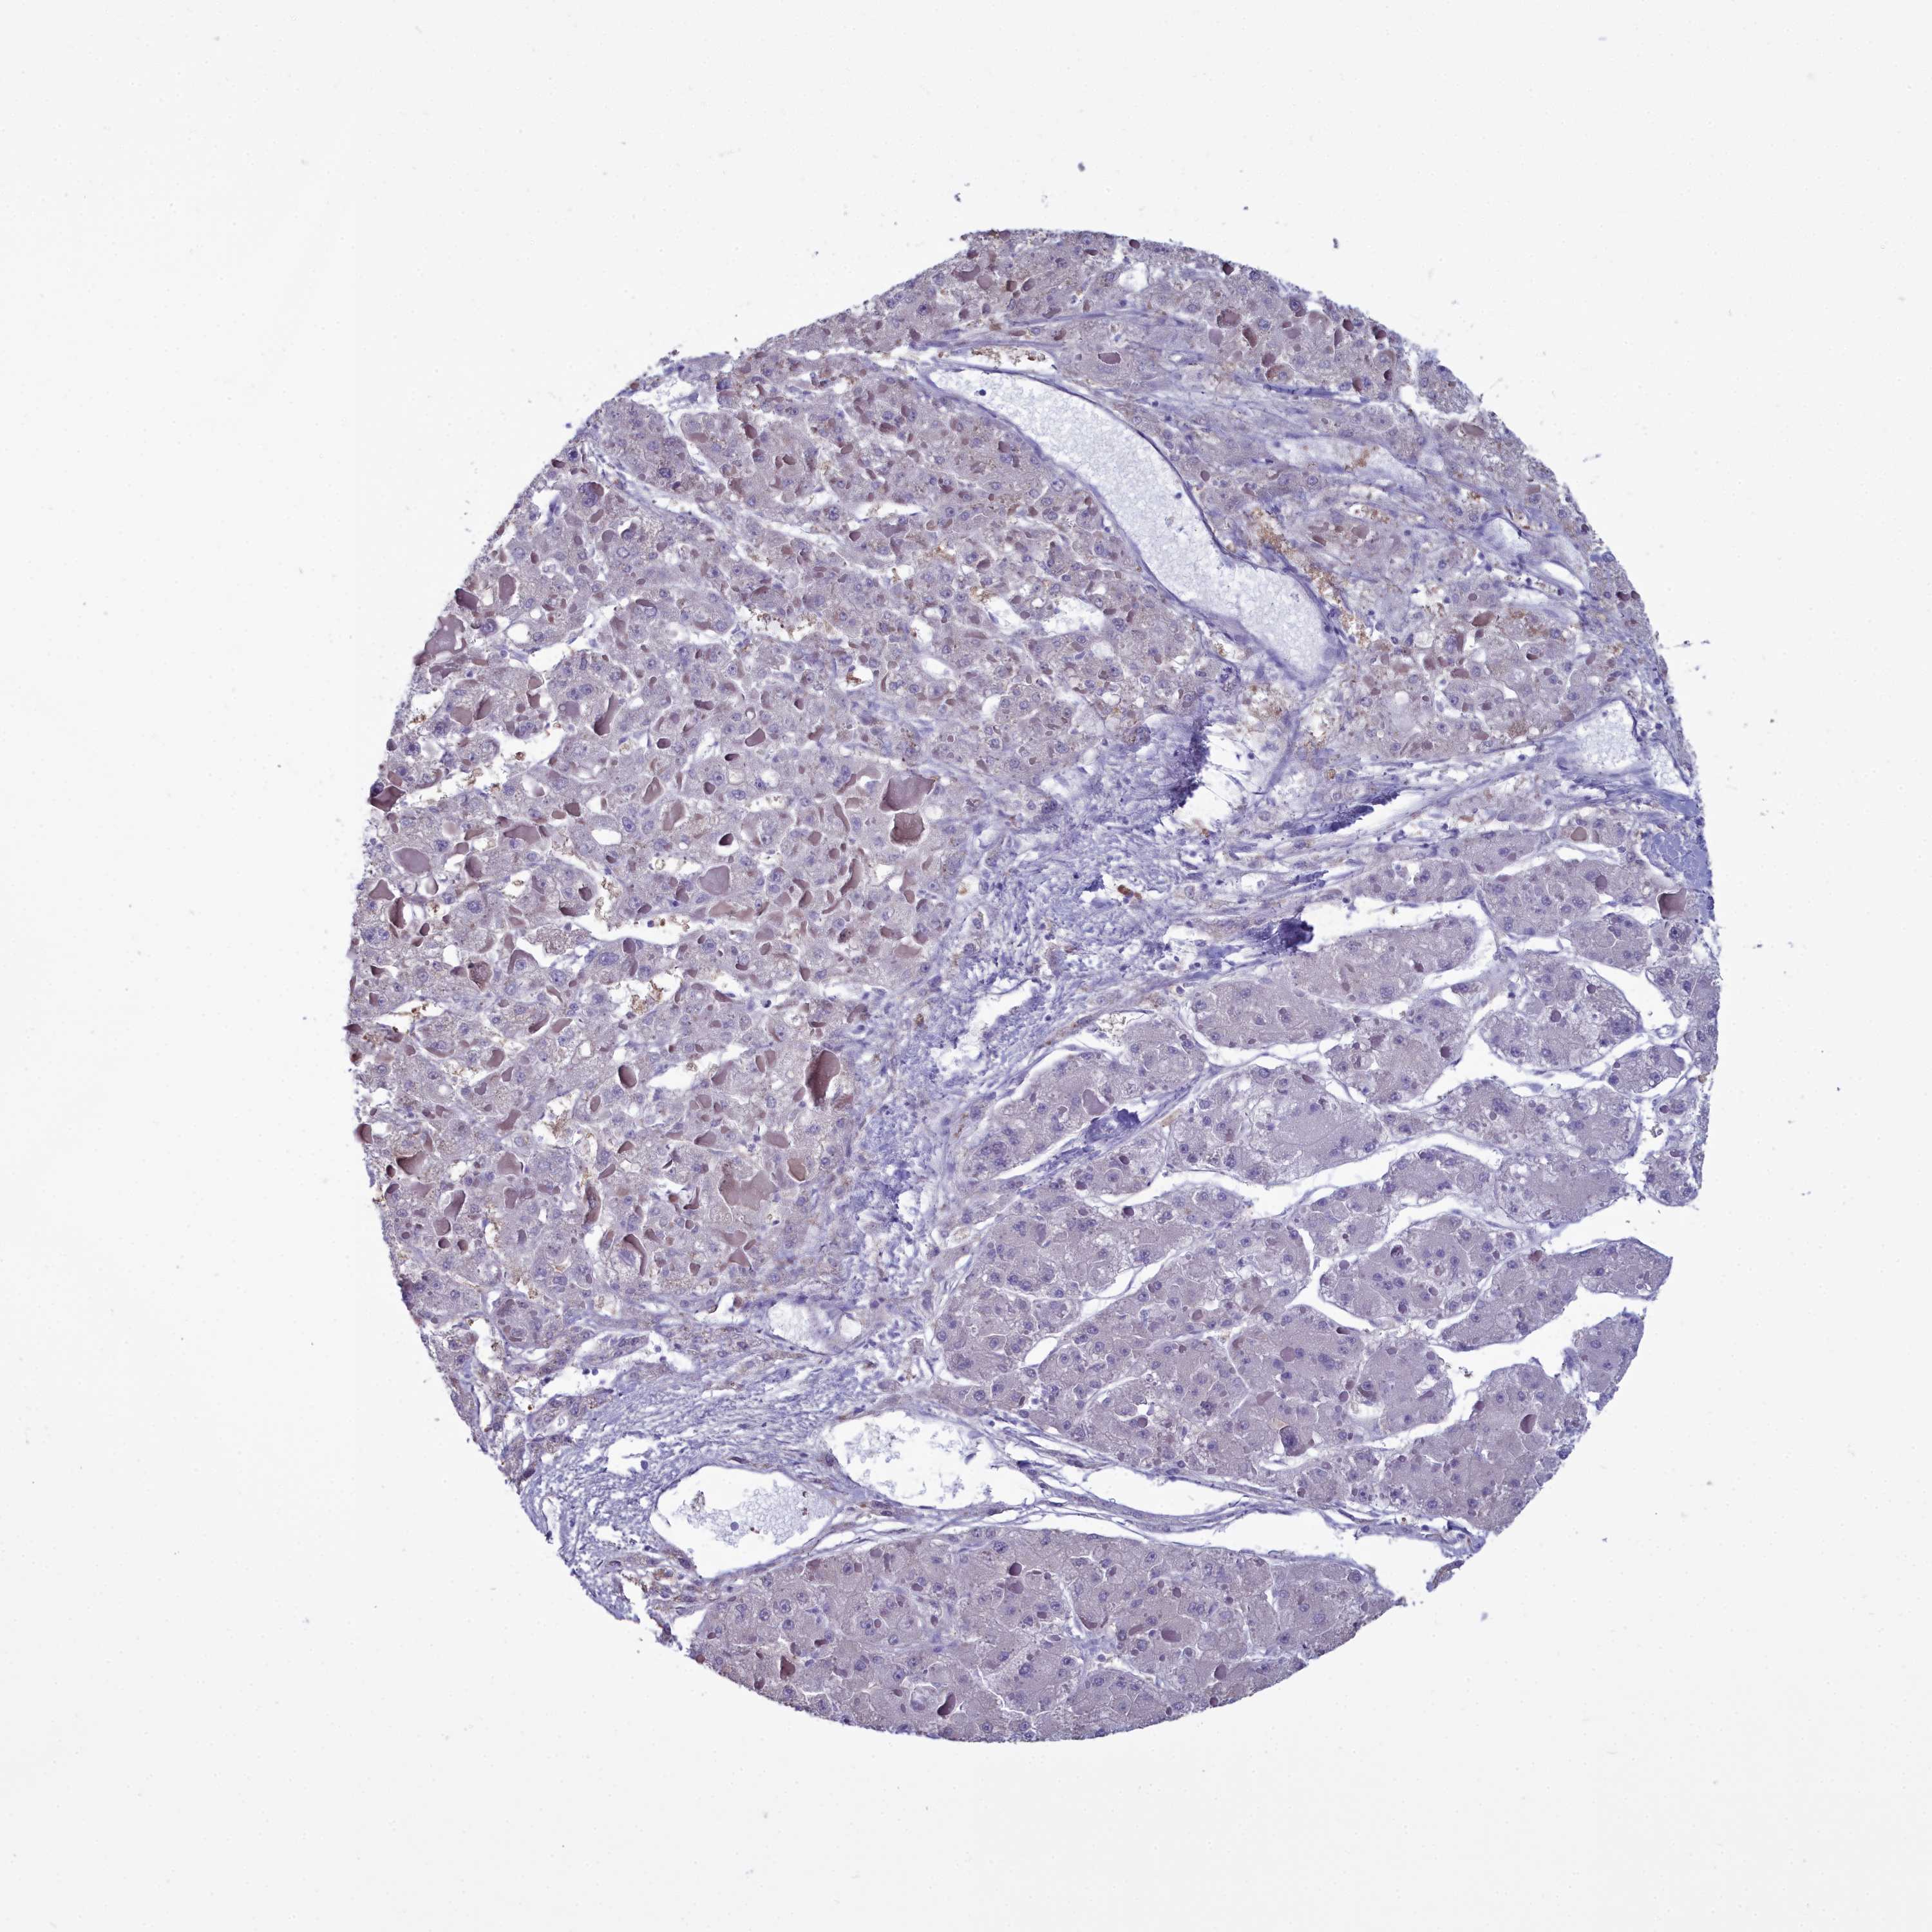

LIVER CANCER - Protein expressioni

A mouse-over function shows sample information and annotation data. Click on an image to view it in a full screen mode. Samples can be filtered based on level of antibody staining by selecting one or several of the following categories: high, medium, low and not detected. The assay and annotation is described here.

Note that samples used for immunohistochemistry by the Human Protein Atlas do not correspond to samples in the TCGA dataset.

Antibody stainingi

Antibody staining in the annotated cell types in the current human tissue is reported as not detected, low, medium, or high, based on conventional immunohistochemistry profiling in selected tissues. This score is based on the combination of the staining intensity and fraction of stained cells.

Each image is clickable and will lead to virtual microscopy that enables deeper exploration of all samples and also displays staining intensity scores, fraction scores and subcellular localization as well as patient and tissue information for each sample.

Antibody HPA039061

Antibody HPA039062

Antibody CAB015442

Antibody CAB022600

Cholangiocarcinoma

Carcinoma, Hepatocellular, NOS